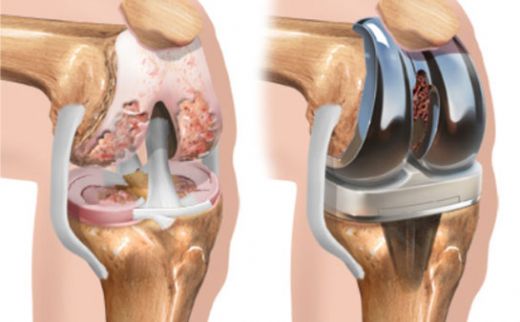

Diz kıkırdak aşınması, diz eklemindeki kıkırdak dokusunun zamanla bozulması ile ortaya çıkan bir durumdur. Yaş, aşırı kullanım, yaralanmalar ve obezite gibi faktörler bu durumu tetikler. Belirtiler arasında ağrı, sertlik ve hareket kısıtlılığı yer alır. Tedavi yöntemleri ise ilaç, fiziksel terapi ve cerrahi seçenekleri içermektedir. Bu yazıda, diz kıkırdak aşınmasının belirtileri, nedenleri ve tedavi yöntemleri detaylı bir şekilde ele alınmaktadır.

Diz Kıkırdak Aşınması Belirtileri ve Tedavisi Diz kıkırdak aşınması, diz ekleminde bulunan kıkırdak dokusunun zamanla bozulması ve incelmesi durumudur. Bu durum, genellikle yaşlanma, aşırı kullanım, yaralanmalar ve obezite gibi faktörlerden kaynaklanmaktadır. Kıkırdak, eklemler arasında amortisör görevi görerek, kemiklerin birbirine sürtünmesini önler. Kıkırdak aşınması, dizdeki ağrı, sertlik, şişlik ve hareket kısıtlılığı gibi belirtilerle kendini gösterir. Bu makalede, diz kıkırdak aşınmasının belirtileri, nedenleri ve tedavi yöntemleri üzerinde durulacaktır. 1. Diz Kıkırdak Aşınmasının Belirtileri Diz kıkırdak aşınmasının belirtileri, hastalığın ilerlemesine bağlı olarak değişiklik gösterebilir. Genel olarak görülen belirtiler şunlardır:

4. Tedavi Yöntemleri Diz kıkırdak aşınması tedavisi, hastanın durumuna ve aşınmanın derecesine bağlı olarak değişmektedir. Tedavi yöntemleri şunları içermektedir: